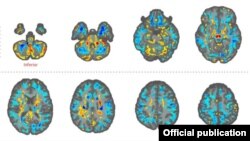

Imágenes de cerebros de algunos de los diplomáticos estadounidenses, hechas con técnicas avanzadas de resonancia magnética (Foto: Journal of the American Medical Association, JAMA).

Las imágenes revelaron “diferencias significativas en el volumen de materia blanca cerebral total, [en] volúmenes locales de materia blanca y gris”, y en la integridad microestructural del tejido del cerebelo. También mostraron diferencias de “conectividad en las subredes auditivas y visoespaciales, pero no en la subred de control ejecutivo”.

“Lo que pueden decirnos las imágenes cerebrales [de resonancia magnética] es si le pasó algo al cerebro”, le dijo a The New York Times la doctora Ragini Verma, profesora de Radiología de la Universidad de Pensilvania y la encargada del estudio. “Y la respuesta es que sí […], pero no sé la causa. Las imágenes por sí mismas no pueden decirnos eso”.